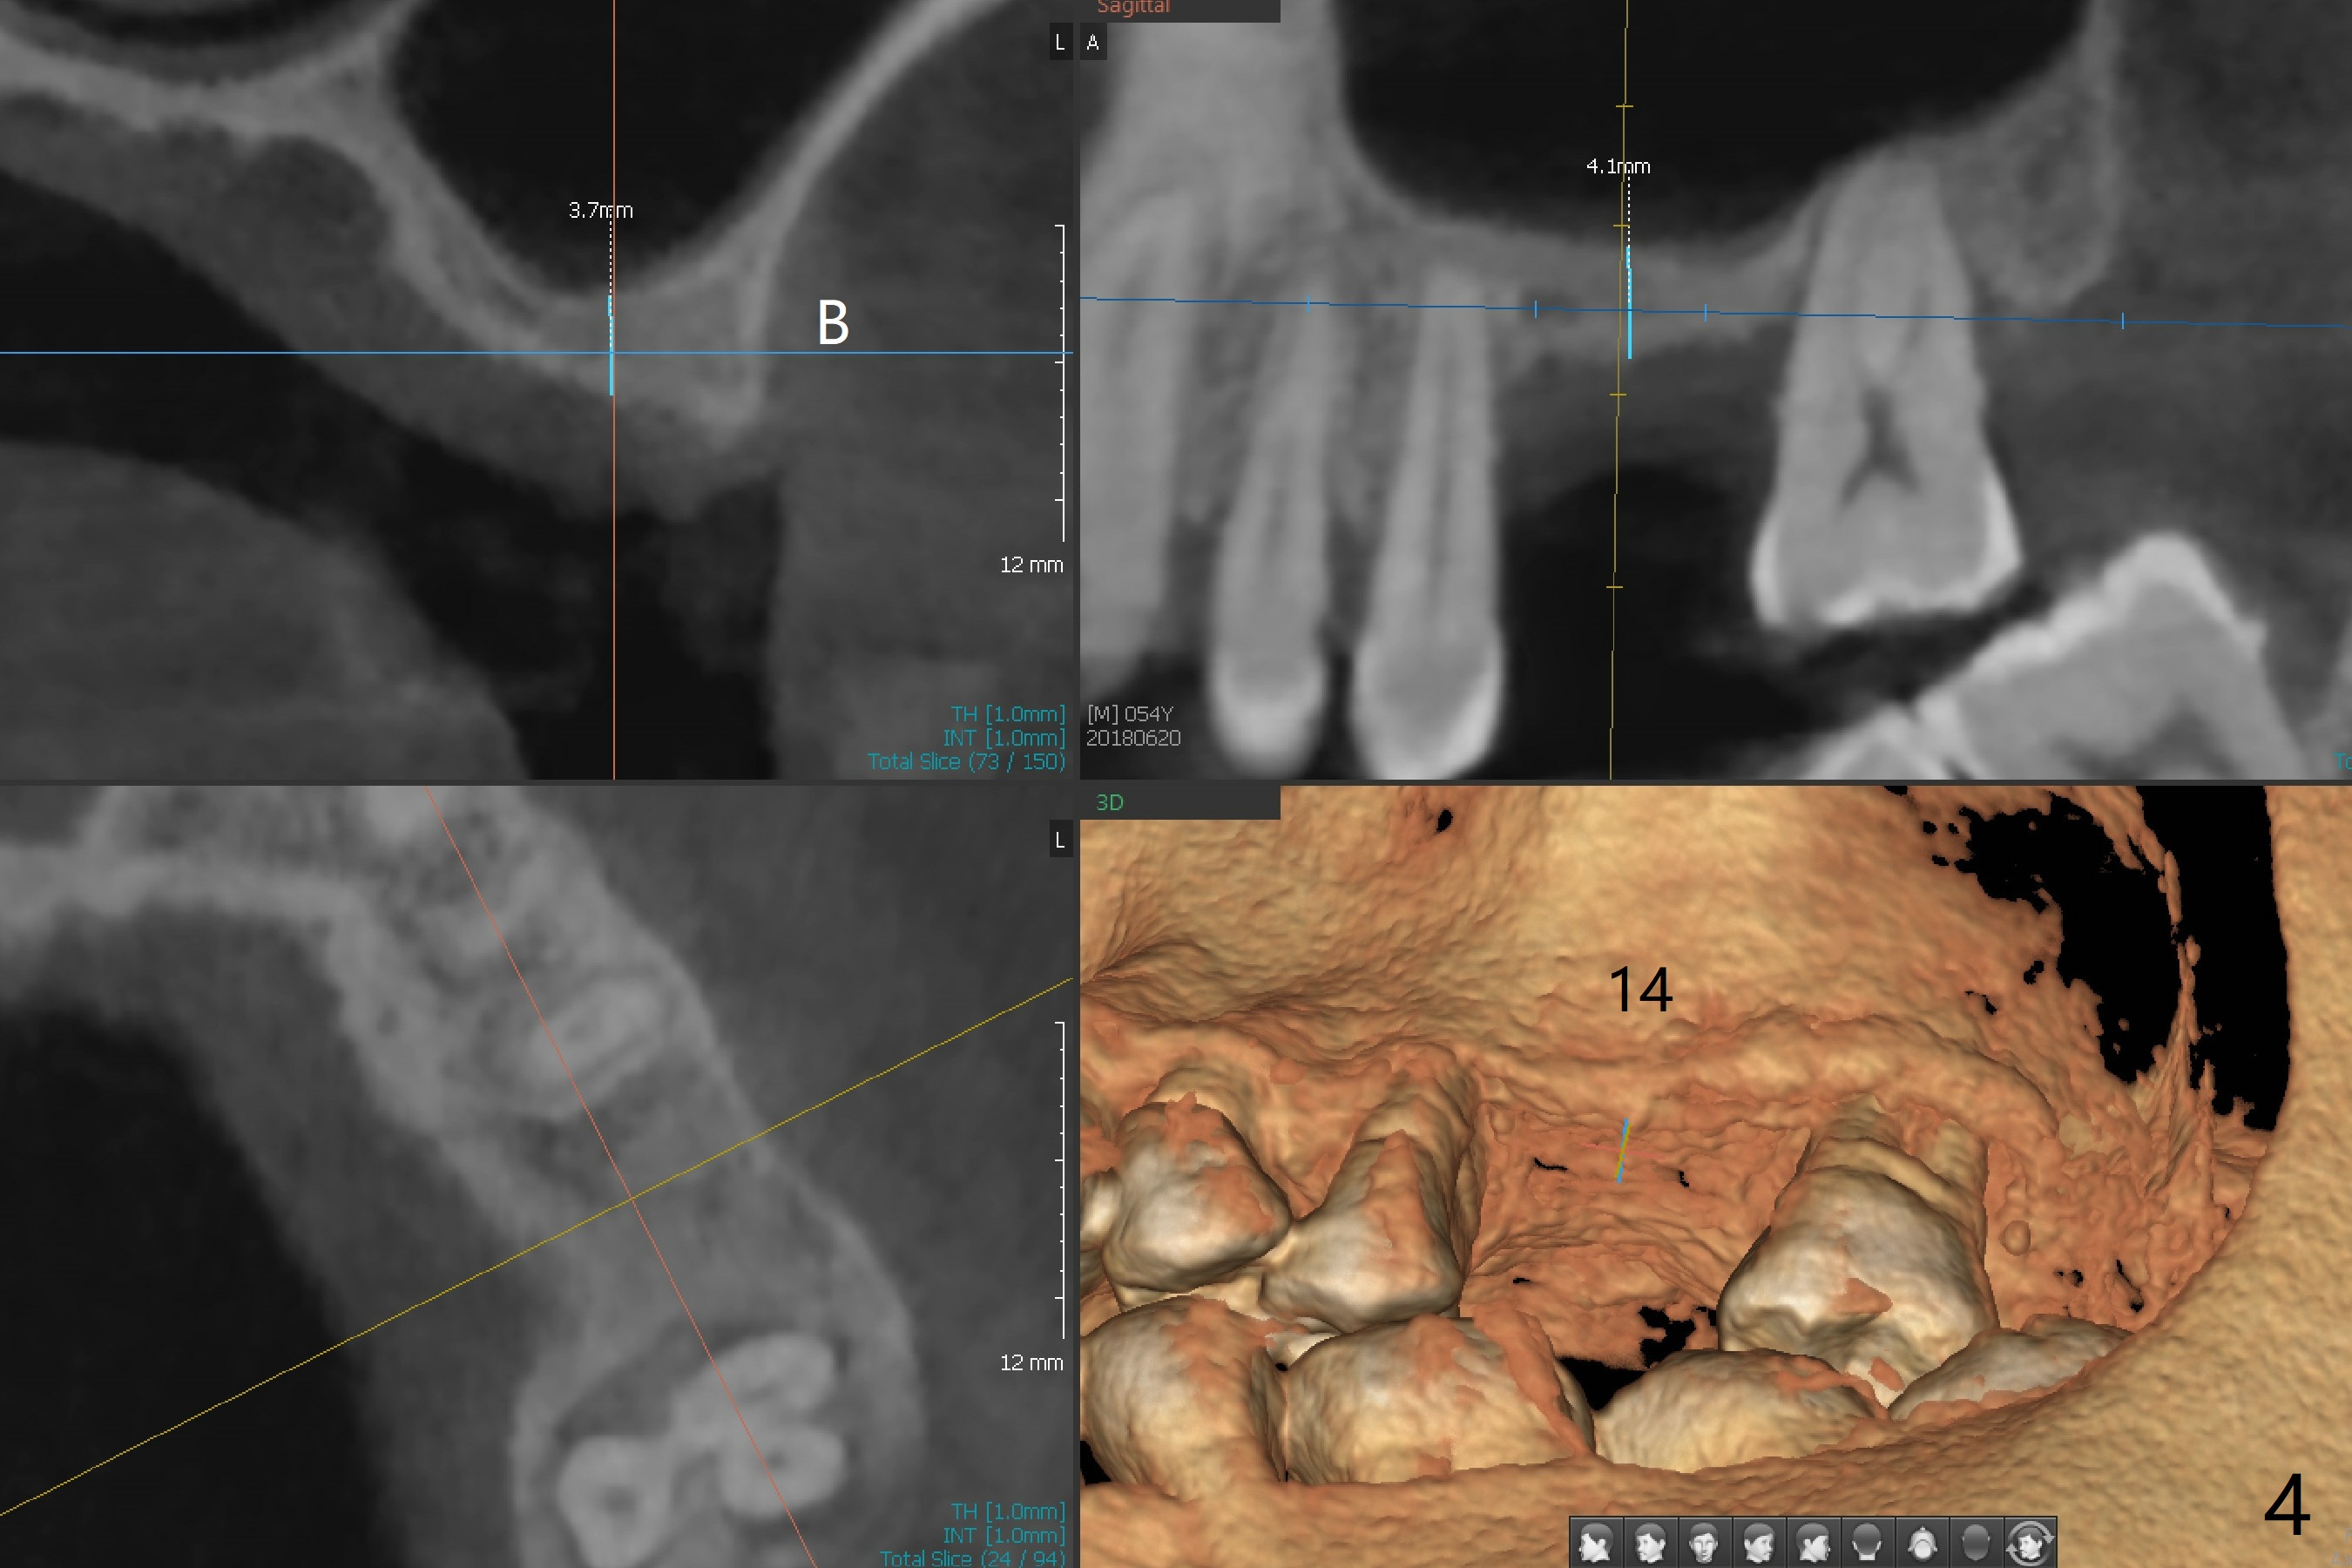

A 54-year-old man presents to office with a request to get a tooth back in the upper left posterior region (Fig.1 #14, wearing RPD). Upon examination, he feels that the tooth #2 is mobile, requiring more urgent care (Fig.2). The infection also involves the tooth #1. Extraction of the latter seems to be imminent. At either site, bone height is limited. Sinus lift is expected with PRF. Place an implant that just passes the sinus floor for stability, e.g., 5-6x10 mm at #2 (Fig.3), but not too long into the sinus. At the 2nd stage (Fig.4), use Magic drill with 2 mm stopper as a tissue punch. Then with 3 mm stopper start osteotomy, followed by Magic lifter, PRF/bone graft and dummy implant or tap. More bone graft and definitive implant. In fact the patient wants to have #14 implant first.